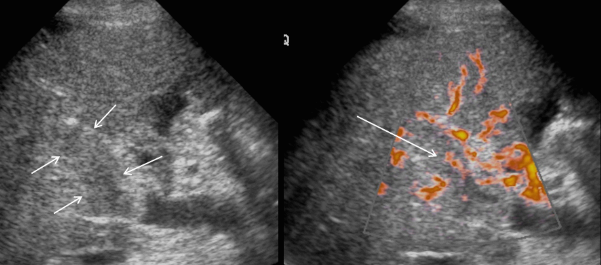

US finding

- 동일한 크기의 다발성 종괴가 나타난다.

- bull's eys sign (종양 변연에 중심부가 고에코이고 경계부가 저에코인 두꺼운 띠가 보인다)

- cluster sign (종양이 융합하여 분엽모양을 이루어 마치 포도송이 모양을 나타낸다)